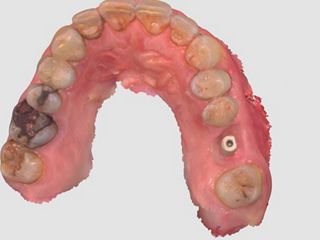

5. Occlusal view after atraumatic tooth extraction.

5

8. Occlusal view of the composite socket sealing with a 3mm provisional titanium retained SSA as fabricated by Gary Finelle.

8